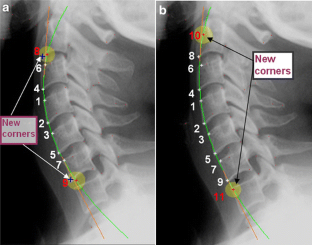

This study was conducted to evaluate a new method used to calculate vertebra orientation in medical x-ray images. The goal of this work is to develop an x-ray image segmentation approach used to identify the location and the orientation of the cervical vertebrae in medical images. We propose a method for localization of vertebrae by extracting the anterior—left—faces of vertebra contours. This approach is based on automatic corner points of interest detection. For this task, we use the Harris corner detector. The final goal is to determine vertebral motion induced by their movement between two or several positions. The proposed system proceeds in several phases as follows: (a) image acquisition, (b) corner detection, (c) extracting of the corners belonging to vertebra left sides, (d) global estimation of the spine curvature, and (e) anterior face vertebra detection.

Fig 1